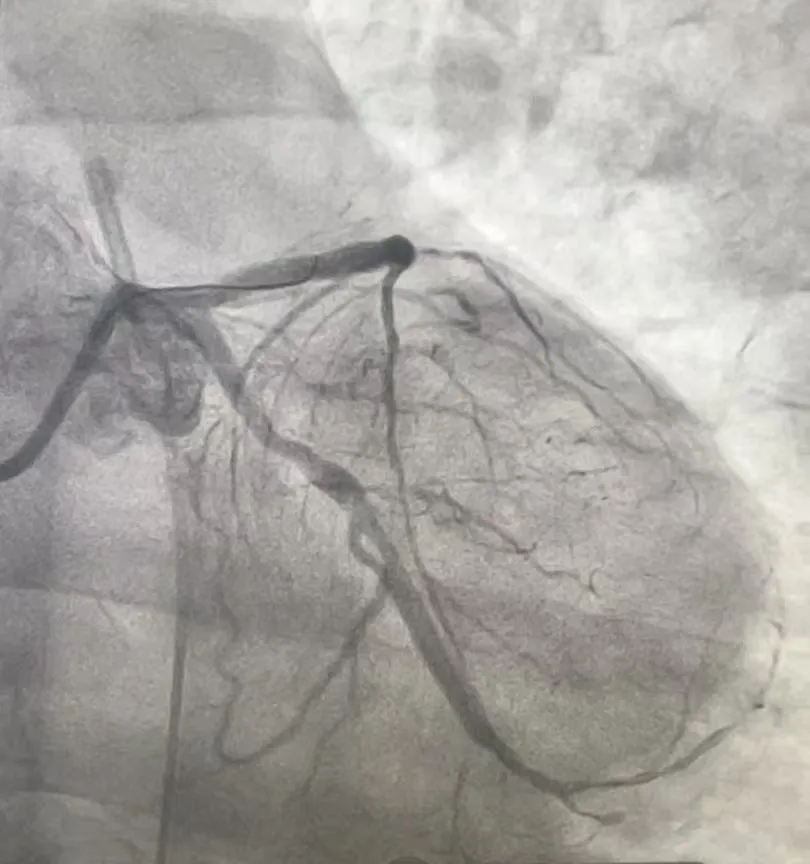

造影揭秘:三支血管“堵”成“危机四伏”

心脏血管造影检查提示,张先生的三支主要血管均存在严重病变。

• 前降支近段完全闭塞,该血管心脏供血的“主干道”之一,负责左心室前壁血液供应,堵塞后极易引发大面积心梗;

• 回旋支中远段完全闭塞,供应心脏侧壁血液,闭塞会加重心肌缺血范围;

• 右冠状动脉中远段弥漫性狭窄,最重处达70%-80%,虽未完全堵死,但狭窄严重,随时可能进展为急性闭塞。

(术前影像)

患者前降支和回旋支同时完全堵塞,相当于心脏的两条重要“高速公路”彻底中断,仅靠右冠残余血流勉强维持,随时可能猝死。